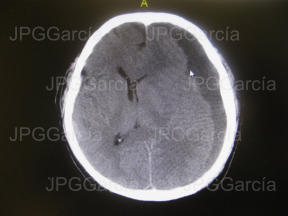

Estudio tomográfico prequirúrgico